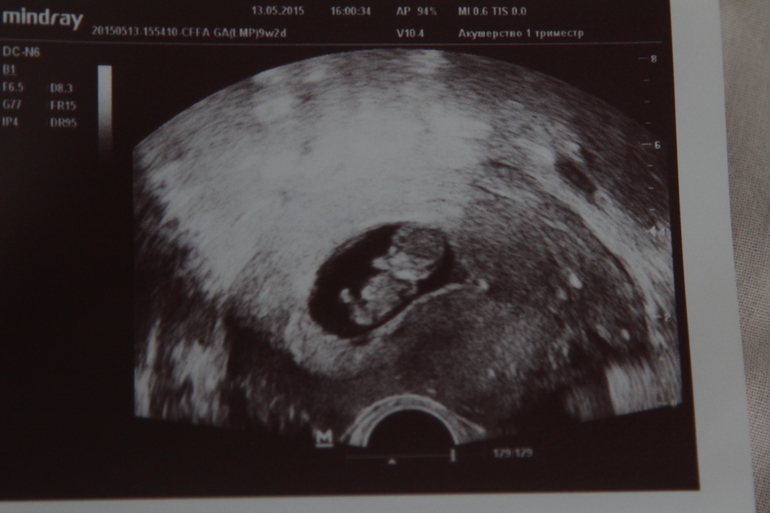

сегодня сходила на узи 9+3

УЗИ, КТГ, доплерВчера заметила, что тошнота отступает, а сегодня только запахи чувствую сильно, но уже не тошнит, хотя и токса зверского не было. С сыном было всё жёстче тогда. Вообщем решила, что пора бы на учёт вставать, сдаваться. Поэтому пошла на узи, благо делают в нашем доме, кабинет платный. Волнительно было очень, 8 лет бесплодия, последняя беременность замершая, оставили отпечаток в памяти. Последнее узи было 4 недели назад, тогда ещё эмбриона не разглядели. А тут сразу человечек, да ещё и ручками ножками машет))) Словами не передать мои чувства, я его уже люблю! С сыном такого не было, глупая была наверное, многого не понимала тогда, 12 лет назад, но и страхов не было... А сейчас чувствительная очень, да и понятно столько слёз было пролито, и всего остального пройдено. По узи всё хорошо, по сроку день в день.

Вот такой мой маленький человечек))))))))